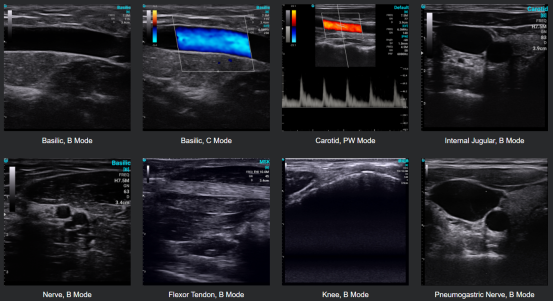

CHISON SonoEye 采用先进的超声波技术来产生高质量的图像。该设备具有一个传感器,可以发射高频声波,穿透身体并反射回设备,从而产生内部结构的图像。该设备还使用复杂的算法来处理图像,产生准确的结果。为了保证测量过程中的准确性,SonoEye配备了很多智能功能,例如Auto IMT、PW AutoTrace、专业肺部软件、针引导软件等。您会发现进行精确测量是一件如此简单快捷的事情。

SonoEye 手持式超声仪适用于各种临床应用,包括 MSK, 心脏病学, 特快专递, 麻醉, 妇产科, 整形外科, 和 血管评估等。